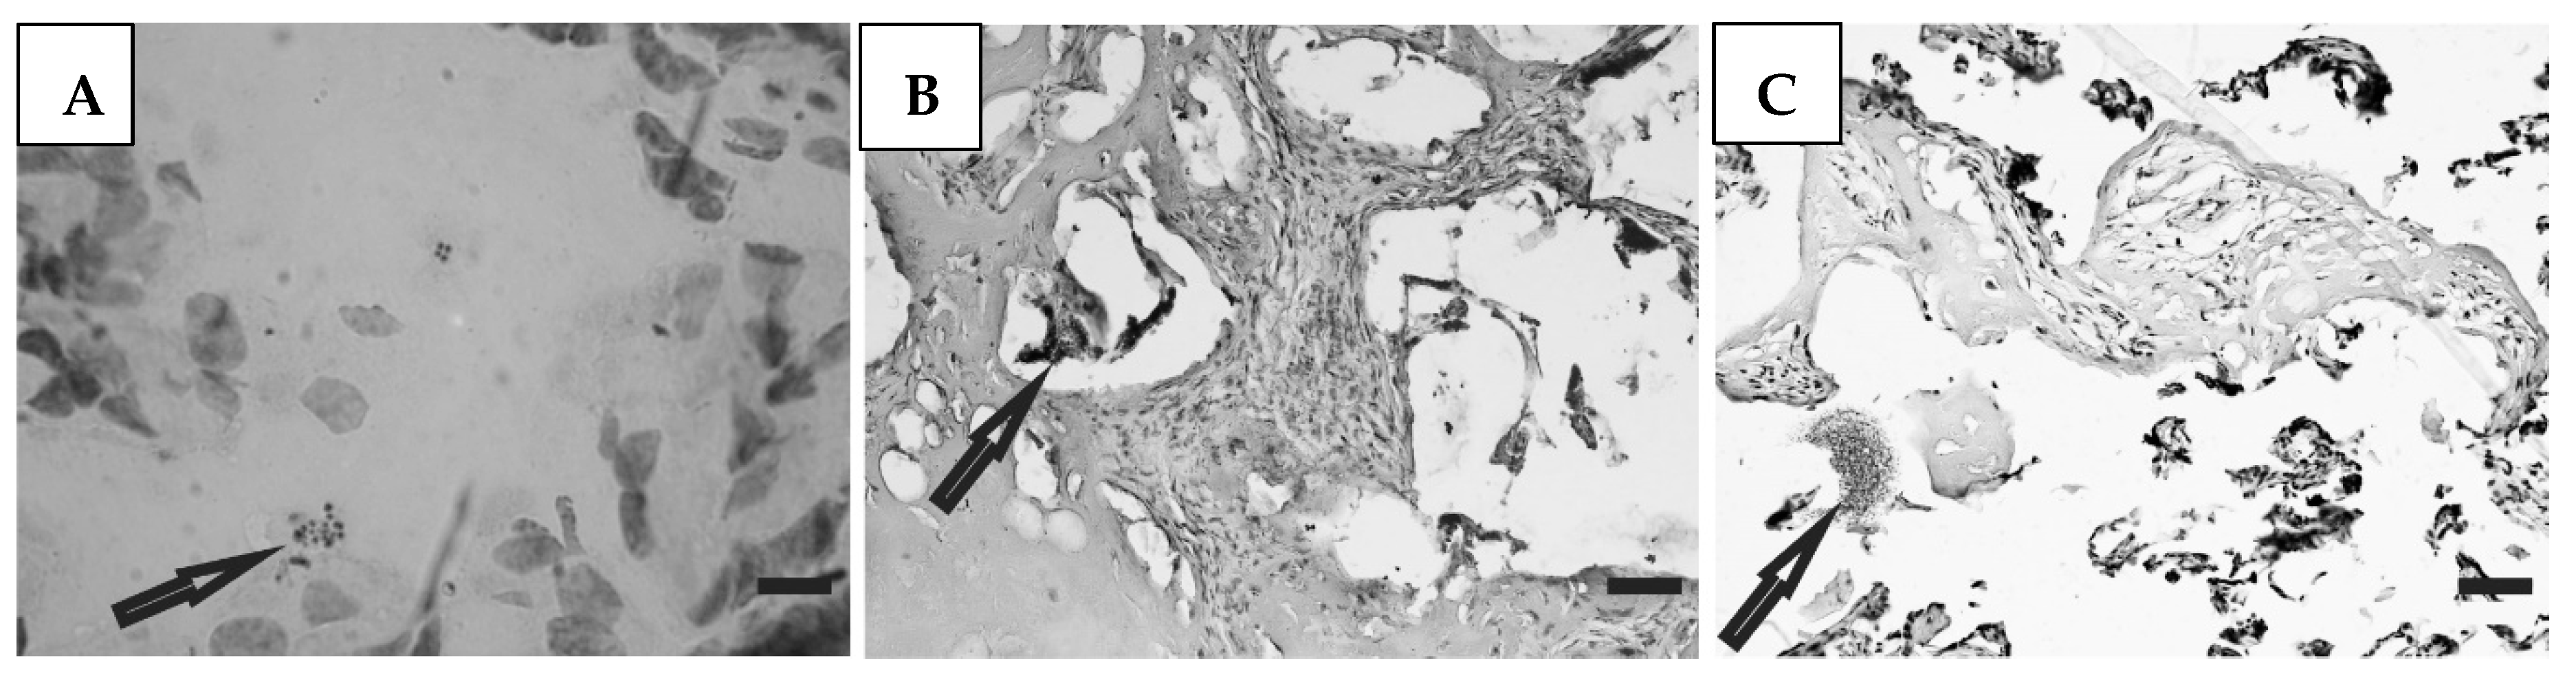

3.5. Histological Studies

Histological preparations of placental tissue sections representative of non-transmitter and transmitter mothers are shown in Figure 2 and Figure 3. Different forms of the parasite were detected through the microscopic observation of chorionic villous human placenta from these mothers. Amastigote nests were observed in preparations from non-transmitter (Figure 2A,B) and transmitter (Figure 3A) mothers, while released parasites were found in placentas from non-transmitter (Figure 2C) and transmitter (Figure 3B,C) mothers.

Figure 3.

Histological section of the placenta from a transmitter mother. Arrows point to (A) amastigote nest; and (B,C) released parasites (H&E). Scale bar: 25 μm.

Part of the focus of this study was the evaluation of parasite load in the congenital transmission process, through the histological and molecular analyses of placental tissue samples. Patterns of amastigote nests and free parasites were observed in histological samples of infected mothers. However, as determined by RT-PCR analyses suggesting live parasites in the placenta, samples with a higher and lower prevalence of parasite load corresponded with infected and non-infected newborns, respectively. We observed that the interplay between the level of parasitemia and the production of IFN-γ determines the occurrence or absence of congenital infection. Therefore, when parasitemia diminishes the stimulus for the production of this cytokine diminishes, there is less control of parasite load, and congenital infection occurs. Conversely, when parasitemia rises, production of IFN-γ increases, and parasite load and congenital infection are controlled.